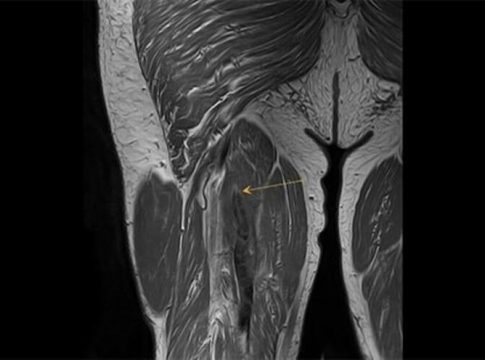

Al respecto, el doctor Mostien y sus compañeros del Hospital Jessa (en Hasselt-Bélgica) y la Universidad de Hasselt tomaron biopsias musculares de pacientes con Covid en estado crítico antes y después de la admisión a cuidados intensivos. Un total de 18 pacientes fueron analizados para el proyecto. Concretamente su vasto lateral, el músculo más grande y poderoso del muslo, biopsiado varias veces desde 1-3 días antes de la admisión en la UCI hasta 5-8 días después de la admisión. Los pacientes tenían una edad media de 69 años y el 82 por ciento eran hombres.

Las fibras musculares de Tipo I crecieron un 5,74 por ciento y las fibras de tipo II se contrajeron un 5,17 por ciento. Sin embargo, las fibras de cuatro pacientes aumentaron un 62 por ciento, en las de tipo I, y un 32 por ciento en las de tipo II.